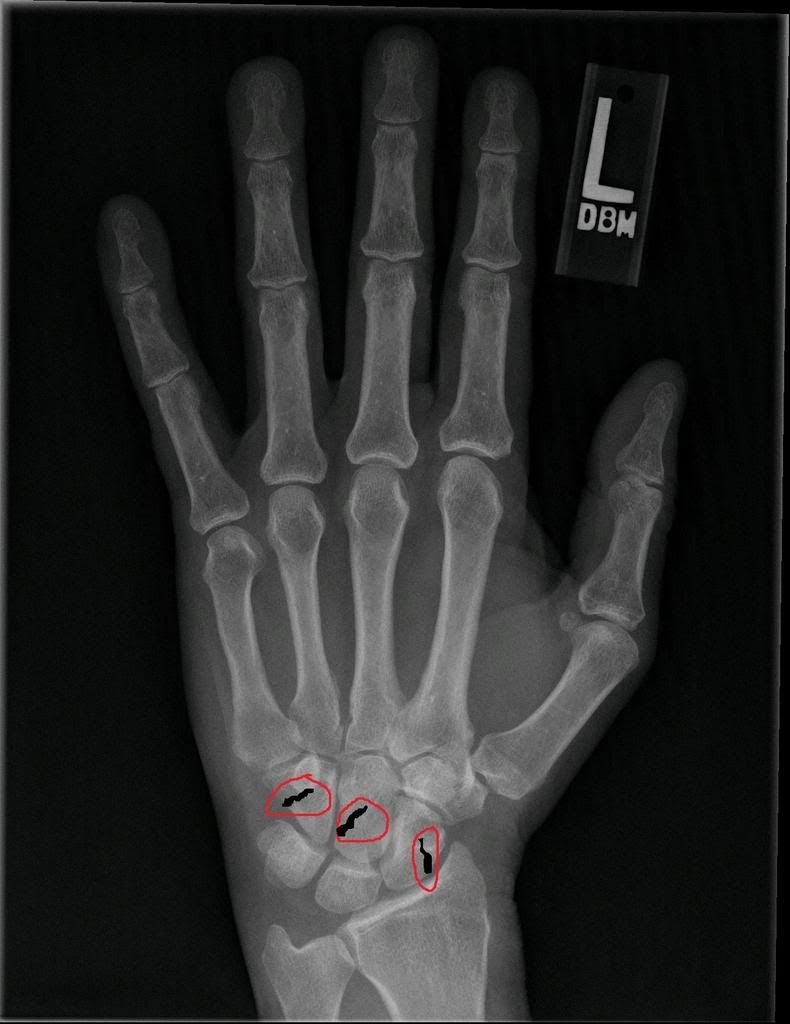

I've got a 3 cracked bones, the Capitate, the Hamate and Trapezoid. I have to get surgery on the 9th of September. They said there's nothing they can do as a bandage will put it at an awkward angle, making it hurt more. All they can do is provide painkillers. So of the reasons may be that I got my wrist jammed in a door, or when playing football I got my wrist stamped on. >.> Surgery is September 9th. This is virtually what the x-ray looked like (Note - it's not my x-ray, Google Images ftw) http://i189.photobucket.com/albums/z229/Fenrir_lolwut/wristxray.jpg Oh and my cousins didn't come up today. It's been delayed until Monday for some reason. Woo! |